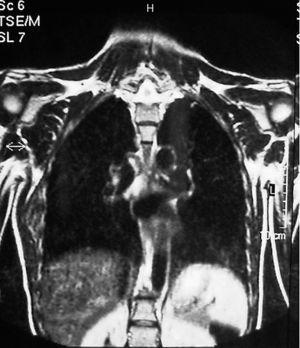

Mujer de 40 años, fumadora, que consultó por un bulto no doloroso en región escapular de un año de evolución que aumentaba de tamaño, alcanzando 7 cm de diámetro. La RMN mostró una tumoración en músculo serrato mayor derecho, en contacto con la pared costal debajo del músculo dorsal ancho que se continúa hasta el músculo subescapular (fig. 1). Era compatible con tumor de alta agresividad, descartandose fibrohistiocitoma u otro sarcoma de partes blandas. Se realizó una biopsia incisional, en anatomía patológica con el resultado de ED. Se practicó una resección marginal, encontrando el tumor ampliamente adherido a la pared torácica y escápula. Se confirmó el diagnóstico de ED tras el análisis de la pieza.

Figura 1. Corte coronal de resonancia magnética nuclear (RMN) en el que se observa un elastofibroma dorsi; se aprecia la tumoración en contacto con la pared torácica bajo el músculo dorsal ancho.